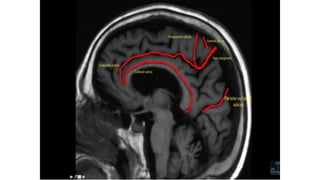

SULCI & GYRI

SULCUS IS THE DEPRESSION [VALLEYS]

AND

GYRUS IS THE RIDGE [HILLS]

Fissure/sulcus Importance

• Interhemispheric fissure • Separates two lobes

 Sylvian fissure/ Lateral

Sulcus

 Frontal to temporal

 Central sulcus  Frontal to parietal

 Callosal sulcus

 Cingulate sulcus

 Interparietal sulcus

 Parieto occipital sulcus

 Calcarine sulcus

12

6

Interhemispheric

fissure

1

3

2

4

5

Superior frontal

Pre central sulcus

Central sulcus

Post central

IPIO

Interhemispheric fissure

The central sulcus-The sigmoid hook

The pars bracket sign- Parieto occipital sulcus

Fish tail- parieto occipital sulcus

Pars marginalis

The bifid sulcus

The intraparietal sulcus